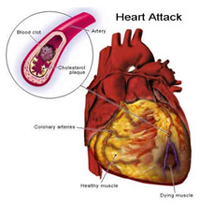

冠狀動脈粥樣硬化的形成,是在上述危險因素作用下,冠狀動脈內皮細胞損傷,脂質侵入冠狀動脈壁沉積,導致平滑肌細胞,單核細胞及成纖維細胞增生,血小板粘附聚集形成血栓,形成突出於管腔的粥樣斑塊,使管腔狹窄,血流受阻,使心肌缺血缺氧。

右冠狀動脈缺血

右冠狀動脈缺血本病病人與其他類型冠心病病人的不同,在於並無臨床症狀,但它又不是單純的冠狀動脈粥樣硬化,因為已有心肌缺血的客觀表現,即:心電圖、放射性核素心肌顯影,或超聲心動圖顯示心臟己受到冠狀動脈供血不足的影響。可以認為是早期的冠心病,但已不一定是早期的冠狀動脈粥樣硬化,它可能突然轉為心絞痛或心肌梗死,亦可能逐漸演變為心肌纖維化出現心臟增大,發生心力衰竭或心律失常,個別病人亦可能猝死。因此,早診斷出這類病人,可為他們創造較早期治療的機會。